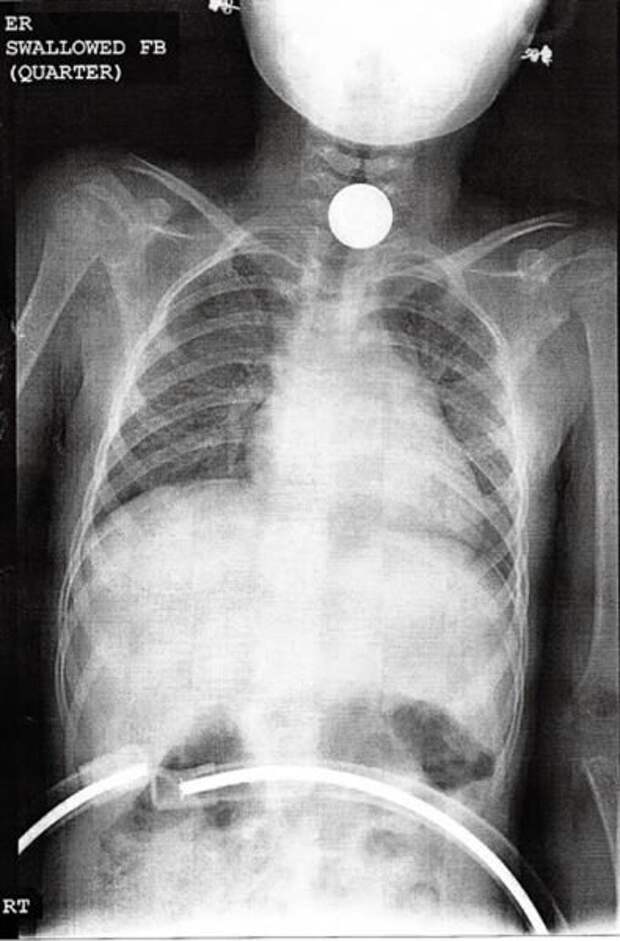

На этом снимке виден четвертак, проглоченный шестилетней девочкой.